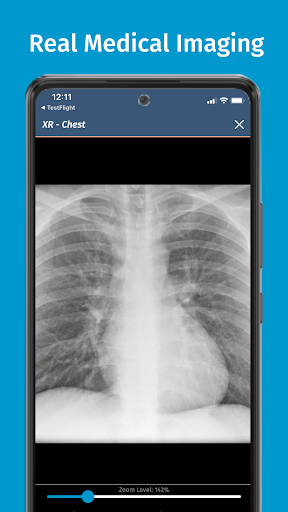

• 200+ thư viện trường hợp được biên soạn và đánh giá bởi các bác sĩ lâm sàng chuyên gia

Được tạo ra bởi các nhà giáo dục y khoa từ một số bệnh viện hàng đầu tại Hoa Kỳ và được các chuyên gia y khoa được cấp phép đánh giá ngang hàng, các mô phỏng của chúng tôi được thiết kế theo các phương pháp thực hành y khoa tốt nhất theo tiêu chuẩn của ngành, đặt ra tiêu chuẩn cao cho sinh viên y khoa và các chuyên gia trên toàn thế giới.